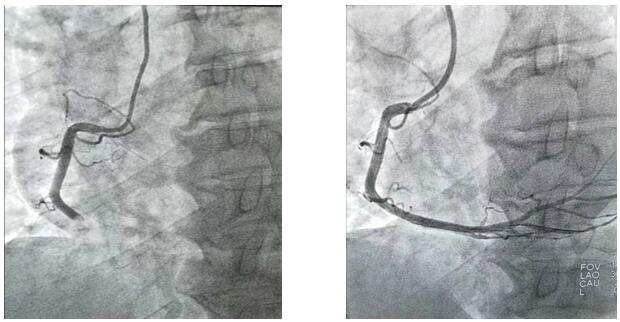

2019年10月1日凌晨1点左右,兴平市人民医院将一位急性心梗病人送至我院,患者胸痛5小时并伴有大汗,心电图显示ST段呈弓背向上型抬高,出现宽而深的Q波和T波倒置。心肌酶及肌钙蛋白升高。心血管病院值班二线立即通知导管室值班医生。“导管室已启动”,一场与死神的博弈即将开始,医护人员“飞毛腿”式赶到导管室,护士开始了准备工作,“液体已配好、除颤仪处于备用状态、急救药品准备完毕”的同时,随着技师“赶快带病人”。医护人员穿上近30斤重的铅衣、洗手、戴口罩,一场没有硝烟的战争正式开始了,消毒、穿刺、造影.....手术紧张而有序的进行着,经过一小时左右的奋力抢救,病人终于脱离了危险。安全送至CCU后,医护人员此时已经筋疲力尽,身上的衣服也已经湿透,但大家还是会共同探讨手术的过程。

凌晨3点,手术室终末消毒工作刚刚结束,“滴滴滴……”胸痛中心来电,启动导管室,医护人员再次穿上铅衣冲向属于自己的特殊战场……10月1日、10月2日、10月3日、10月4日、10月5日、10月6日,我们完成PTCA支架置入术、冠状动脉内溶栓术、PTCA腔内成型术、临时起搏器置入术、冠状动脉内左室造影术及冠状动脉内血管造影术共计心脏介入手术35例。我们永不停息的穿梭与手术间,平凡的本职工作中,与死神赛跑.....挽救了无数名生死垂危的患者,解除患者病痛的同时,还您一个完整、幸福的家!